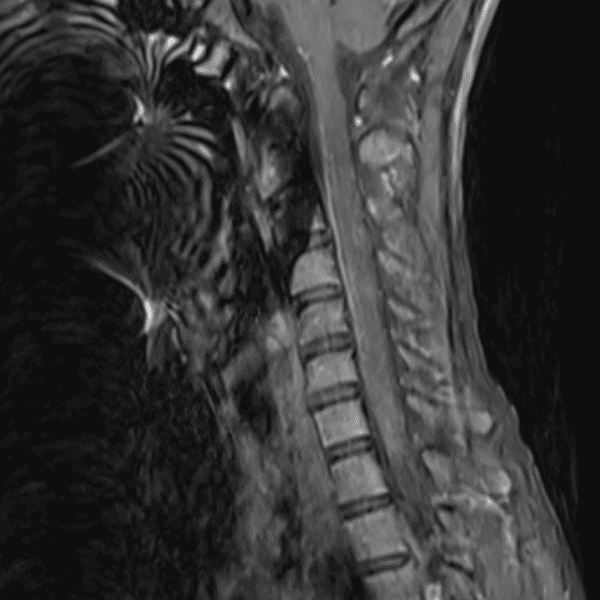

Simulates call by including subtle or difficult cases and some normals.

35 cases